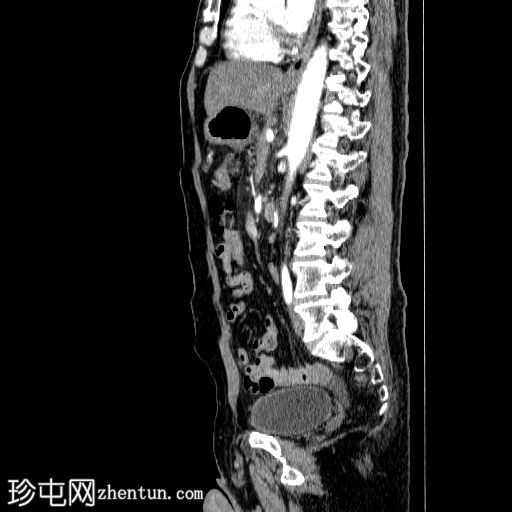

矢状C+动脉期

胰体尾弥漫性增大,特征为胰腺实质低强化,无明显坏死区域。

该病灶与以下表现相关:

胰周筋膜平面边界不清的污迹,无明显壁形成、气室、固体碎片或血液产物。

多个亚厘米大小、非特异性的腹主动脉旁淋巴结和肠系膜淋巴结,可能具有反应性。

病变范围如下:

病变横向延伸至左前肾旁间隙,伴有Gerota筋膜增厚。

病变向下延伸至盆腔。

无肠系膜或脾脏血管阻塞的证据。

未见导管扩张或钙化。